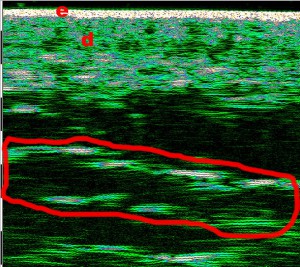

-Lifting με νήματα